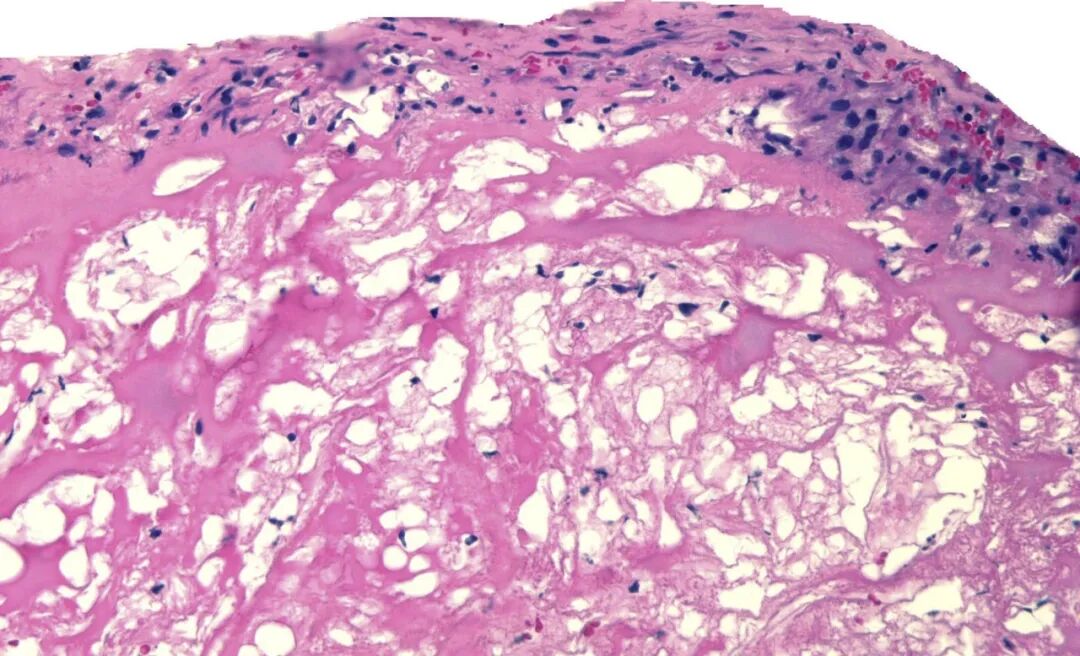

钙化结节与斑块破裂的代表性血管内超声图像。钙化结节为一团突入动脉管腔内的圆形钙化组织(a)。斑块破裂则表现为一个与管腔相通的空腔(星号标记),其上覆有残余的纤维帽碎片(b)。